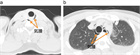

1. 食道破裂(esophageal rupture)、食道穿孔(esophageal perforation)や食道断裂(esophageal disruption)とは、食道壁に全層性に断裂(disruption)や損傷(trauma、injury)が生じた状態である。

1. 胸痛、呼吸困難、ショックなどの症状を呈する。